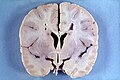

Section with descriptions (WC/SMH)

- Uncus (as in uncal herniation).

- Hippocampus (as in hippocampal sclerosis).

- Longitudinal fissure - divides cerebrum into hemispheres.